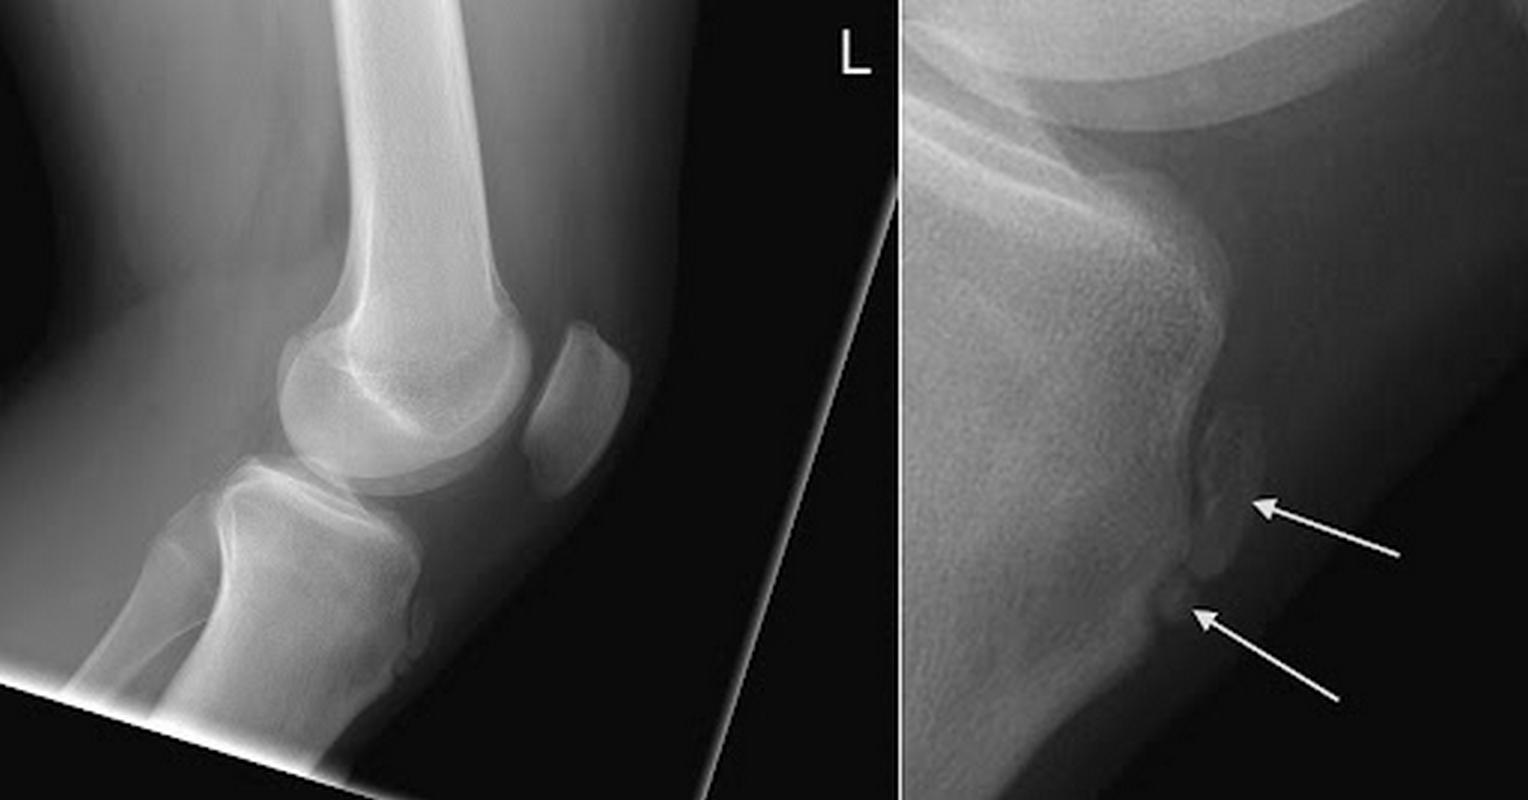

Η διάγνωση βασίζεται κυρίως στην κλινική εξέταση από τον ορθοπαιδικό, σε συνδυασμό με το ιστορικό ηλικίας και αθλητικής δραστηριότητας. Οι ακτινογραφίες χρησιμοποιούνται σε επίμονες ή άτυπες περιπτώσεις, κυρίως για τον αποκλεισμό άλλων αιτιών πόνου στο γόνατο.

Στις περισσότερες περιπτώσεις δεν απαιτούνται εξειδικευμένες απεικονιστικές εξετάσεις.